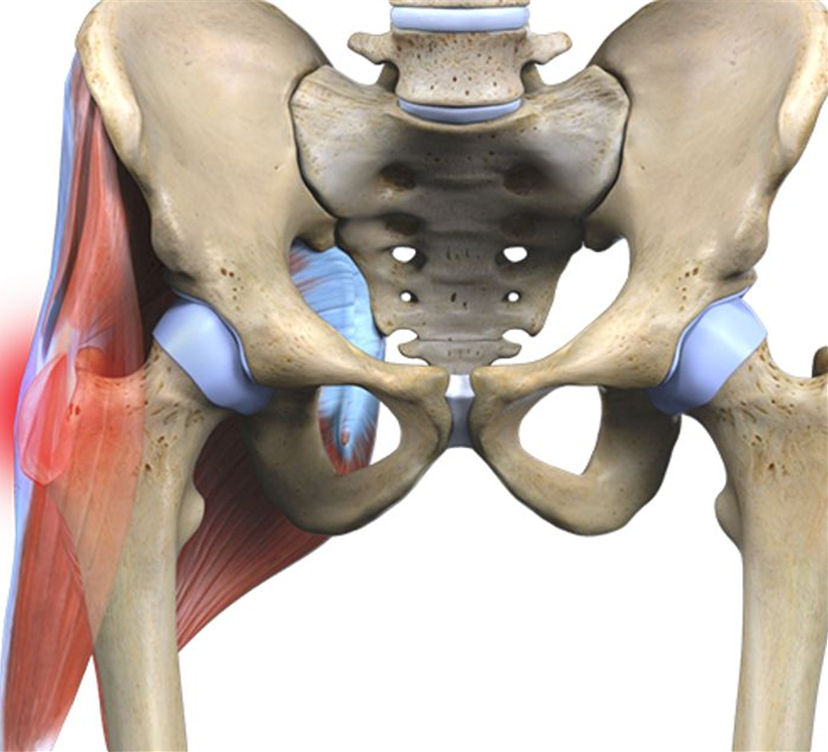

Здоровье суставов: Трохантерит и его влияние на мышцы